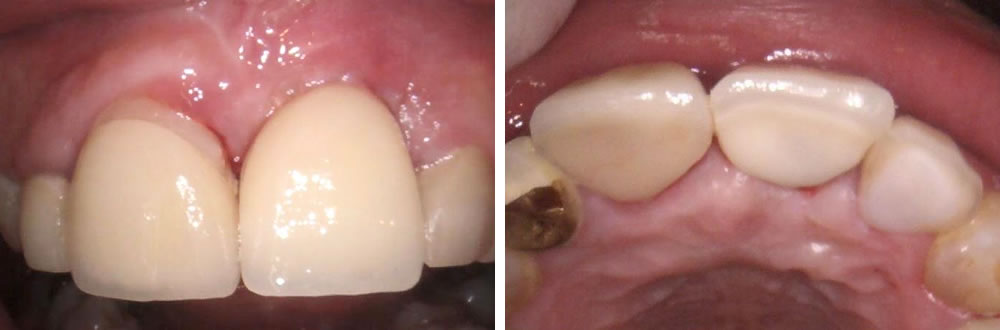

インプラント治療完了後の口腔内写真

歯茎のラインも下がる事なく色合いも自然に完了する事ができ、とても満足をして頂く事ができました。